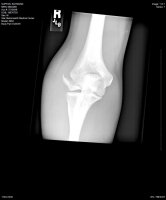

Good to hear you are doing okay and spirits are up.not real bad! bout a 5.

i didnt have time but i tried. mind you i was stuck in the bike anyhow so"i endoed my bike 6-8 feet up at ram jam, put my arms out and got landed on by my bike"

Am I the only one that will say it?.................."Tuck and Roll, Tuck and Roll" "NEVER PUT YOUR ARMS OUT!"

OK, I said it. Sorry for the mishap YD. Speedy recovery to you. One more thing..............................